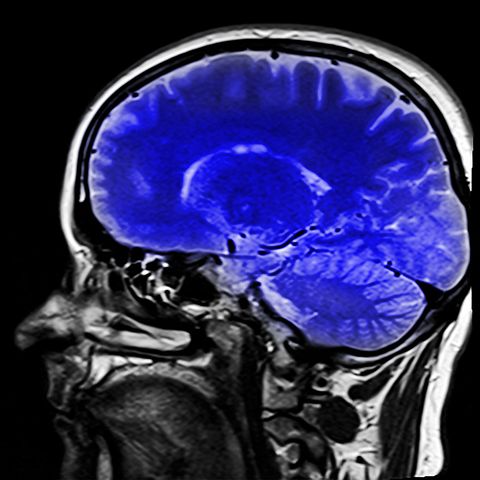

Radiation therapists administer radiation treatment to help fight cancer, including monitoring patients’ progress and reporting this data to the proper medical professionals. They help patients to understand how radiation therapy works by providing explanation and answering questions. They must have the ability to perform X-rays, operate a variety of medical equipment, and report any equipment malfunctions.